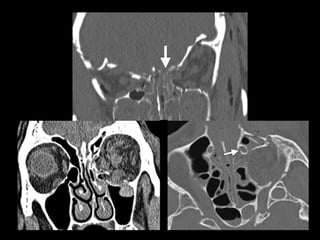

• Blowout

• #30 Trauma directo en ojo Suelo orbitario Hernia muscular Nervio infraorbitario